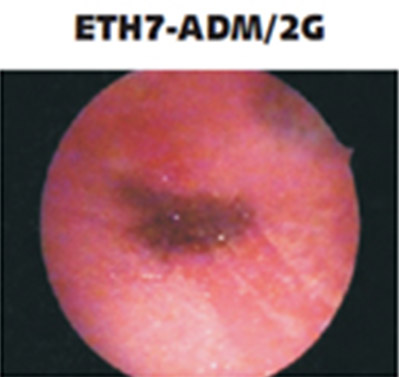

ETH Artıfıcıal Uterus

Dünyanın önde gelen jinekologlarının gözlemlerine göre tasarlanan yapay uterusun patolojileri, vajinal histeroskopide eğitim için, tortuoz serviksin değerlendirilmesi, tanı muayeneleri, biyopsi gibi işlemler, yabancı vücut yapılarının çıkarılması, myomlar, polipler, uterin yanlış biçimlerinin değerlendirilmesi ve düzeltilmesi ve daha birçok işlemin gerçeklemesini sağlar.

Yapay uterusun farklı pataloji seçenekleri ile belirli eğitim amaçlarına olanak sağlamaktadır.